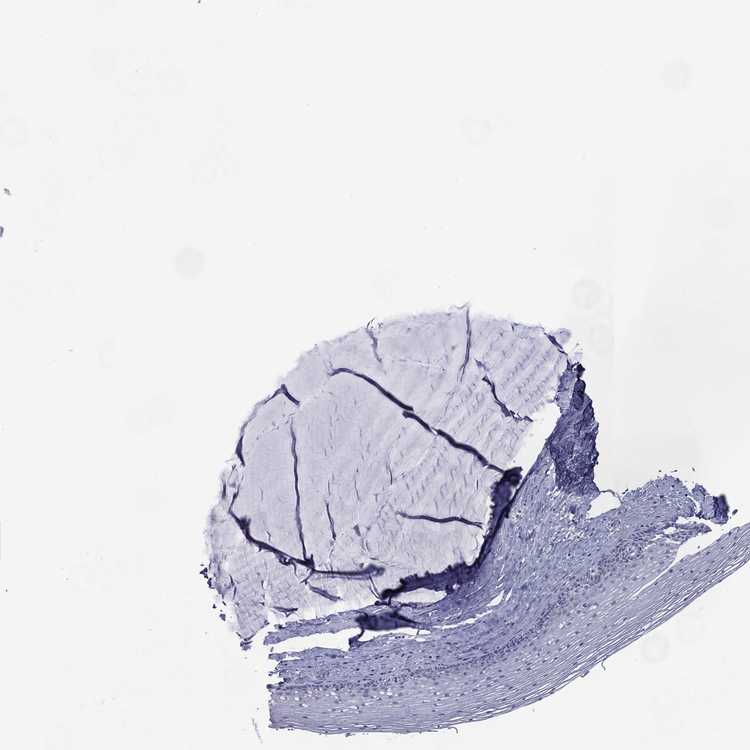

CERVIX - Antibody stainingi

Antibody staining in the annotated cell types in the current human tissue is reported as not detected, low, medium, or high, based on conventional immunohistochemistry profiling in selected tissues. This score is based on the combination of the staining intensity and fraction of stained cells.

Each image is clickable and will lead to virtual microscopy that enables deeper exploration of all samples and also displays staining intensity scores, fraction scores and subcellular localization as well as patient and tissue information for each sample.

Antibody HPA079195

Glandular cells Not detected

Squamous epithelial cells Not detected